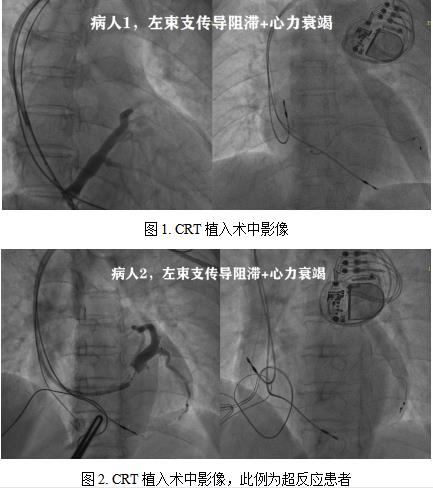

自医院启用以来,我院心血管内科已引进江苏省内第1台抗核磁的心脏除颤器,并有多名患者使用心脏高端起搏器(见图1-图3,其中图3为CRTD)。明显改善生活质量,为生命续航。此类患者往往因为长期未及时纠正心脏传导阻滞,导致心脏明显扩大,且常规心衰药物疗效不佳;经过心脏再同步化治疗后,心电图即刻可见心电信号,心脏工作效能达最大化。这三例患者的手术由资深电生理专家陈弹主任以及董瑞庆博士主导的团队共同完成,每台手术用时约2小时,均成功植入。术中测试参数及术后心电图各项指标均提示手术顺利。尤其第2例为CRT超反应患者,术后心脏功能改善达20%以上。